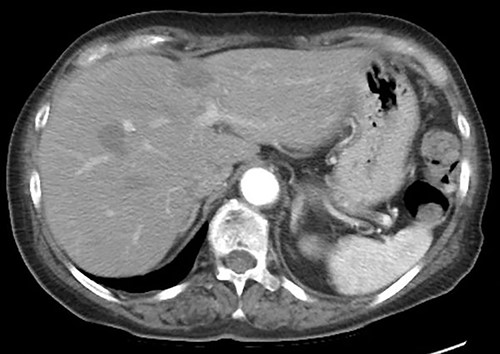

A 75-year-old bedridden woman presented to our hospital with chief complaints of epigastric pain, anorexia and a palpable mass in the epigastric region. She had a history of surgery for meningioma, but no history of abdominal surgery. Ultrasonography revealed a well-defined large cystic lesion with a long diameter of approximately 150 mm in the left liver lobe. Contrast-enhanced computed tomography showed a giant hepatic cyst with an irregular mass in liver segment 4, 20 × 16 cm in size (Fig. 1).

The hepatic cyst compressed the stomach, duodenum, pancreas and gallbladder, and the descending part of the duodenum was difficult to identify because of severe thinning caused by the compression. On magnetic resonance imaging, the giant cyst showed low signal intensity on T1-weighted and high signal intensity on T2-weighted images, and there was a solid component with a high signal on diffusion-weighted images on the dorsal side of the cyst (Fig. 2).